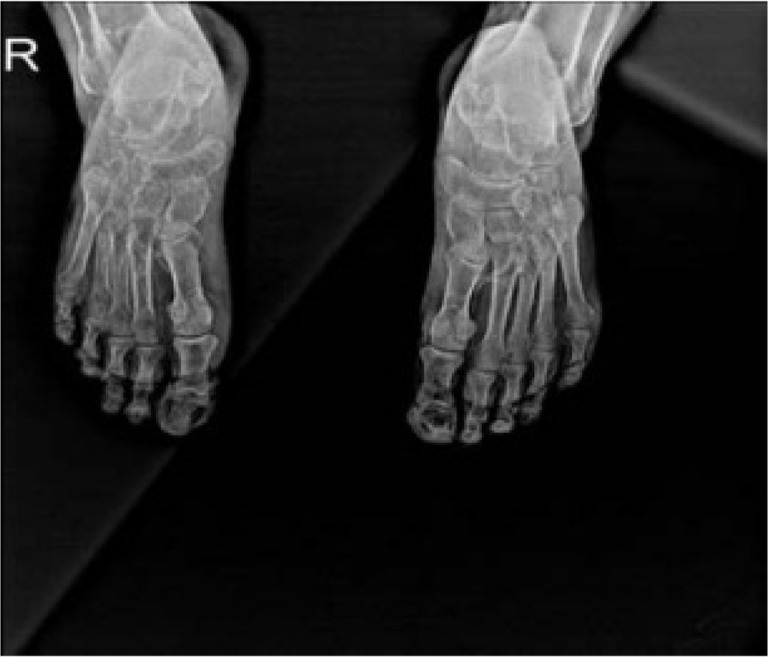

钙化反应,字面意思是“通过钙化来保护”,是一种致命的疾病,其特征是由血管内膜纤维增生、血栓和小动脉钙化引起的皮肤组织缺血性坏死。病理生理学涉及由于血清钙、磷和甲状旁腺激素(PTH)水平异常导致的钙在皮肤、血管间隙和脂肪组织中的积累,特别是在终末期肾病(ESRD)患者中。临床表现通常包括严重的缺血性和神经性疼痛,这些疼痛可能独立于皮肤病变而发生。没有具体的诊断标准或实验室检查;这种疾病主要是根据临床发现来识别的。由于对其机制的了解不完全,没有关于治疗的明确信息;因此,预防钙化反应是至关重要的。在对文献中的病例进行检查后,尽管得到了适当的治疗和护理,但仍观察到34%的死亡率。鉴于其罕见性,钙化反应很容易被忽视。通过对我们风湿病诊所的两例病例的回顾,我们的目的是提高人们对类似血管炎的钙化反应的认识,并促进早期诊断。

Calciphylaxis, which literally means 'protection through calcification', is a fatal disease characterised by ischemic necrosis of cutaneous tissue resulting from vascular intimal fibroplasia, thrombi, and calcifications in the arterioles. The pathophysiology involves the accumulation of calcium in the skin, vascular space, and adipose tissue due to abnormal serum levels of calcium, phosphorus, and parathyroid hormone (PTH), particularly in patients with end-stage renal disease (ESRD). The clinical presentation typically involves severe ischemic and neuropathic pain, which may occur independently of skin lesions. There are no specific diagnostic criteria or laboratory tests; the disease is primarily recognised based on clinical findings. There is no definitive information on treatment due to the incomplete understanding of its mechanism; therefore, the prevention of calciphylaxis is of paramount importance. Upon examination of cases in the literature, a mortality rate of 34% is observed despite appropriate treatment and care. Given its rarity, calciphylaxis is prone to being overlooked. Through this review presenting two cases seen in our rheumatology clinic, our aim is to raise awareness about calciphylaxis which can mimic vasculitis, and promote early diagnosis.